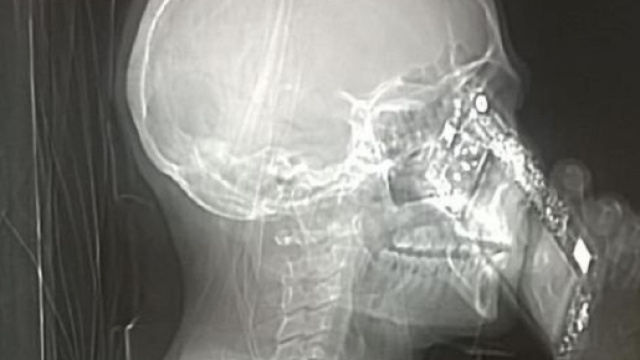

Nonostante l'interruzione dall'esame tomografico, l'apparecchio ha comunque registrato l'immagine che mostra la donna intenta a rispondere al suo cellulare. I medici della struttura ospedaliera di Napoli hanno, cosi, ben pensato di mettere sul web la fotografia non solo per divertire gli utenti, ma anche per avvisare tutta la popolazione di quanto il telefono possa essere pericoloso, soprattutto in momenti delicati come quello di una Tac.

La signora napoletana accusava, ormai da molti giorni, dei forti mal di testa e, dopo innumerevoli accertamenti, i medici dell'ospedale Caldarelli le hanno consigliato di sottoporsi ad una tomografia computerizzata per accertarsi se si trattasse o meno di una cefalea. Come è noto da molti, la prassi della Tac prevede che il paziente metta da parte orecchini, cellulari, collane e quant'altro per fare in modo che l'immagine sia più chiara e precisa possibile. Sfortunatamente, nel corso della scansione tomografica la donna non solo è riuscita a portare il proprio telefono ma ha anche pensato di rispondere ad una chiamata in arrivo.